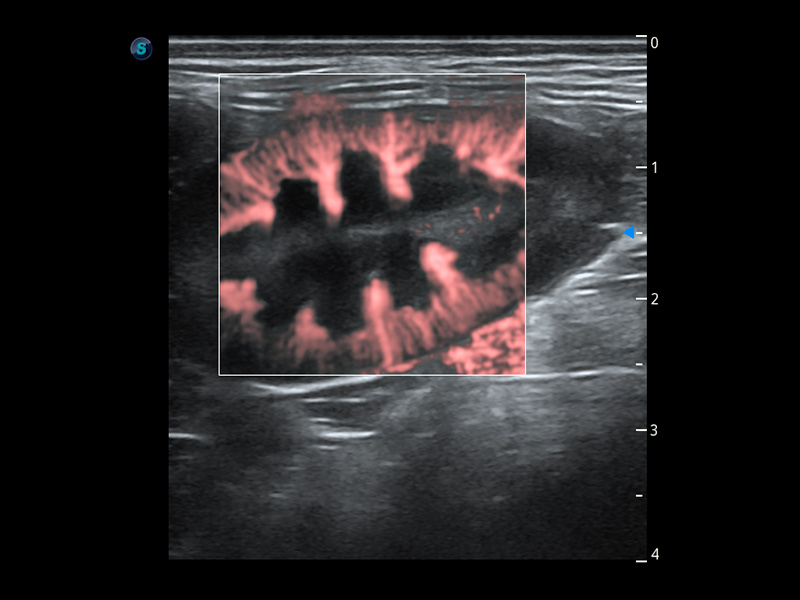

PDI 能量多普勒血流

提供高灵敏度和空间分辦率的血流图像,获得更加真实和丰富的诊断信息。

优异的基础图像

(犬)肾脏血流